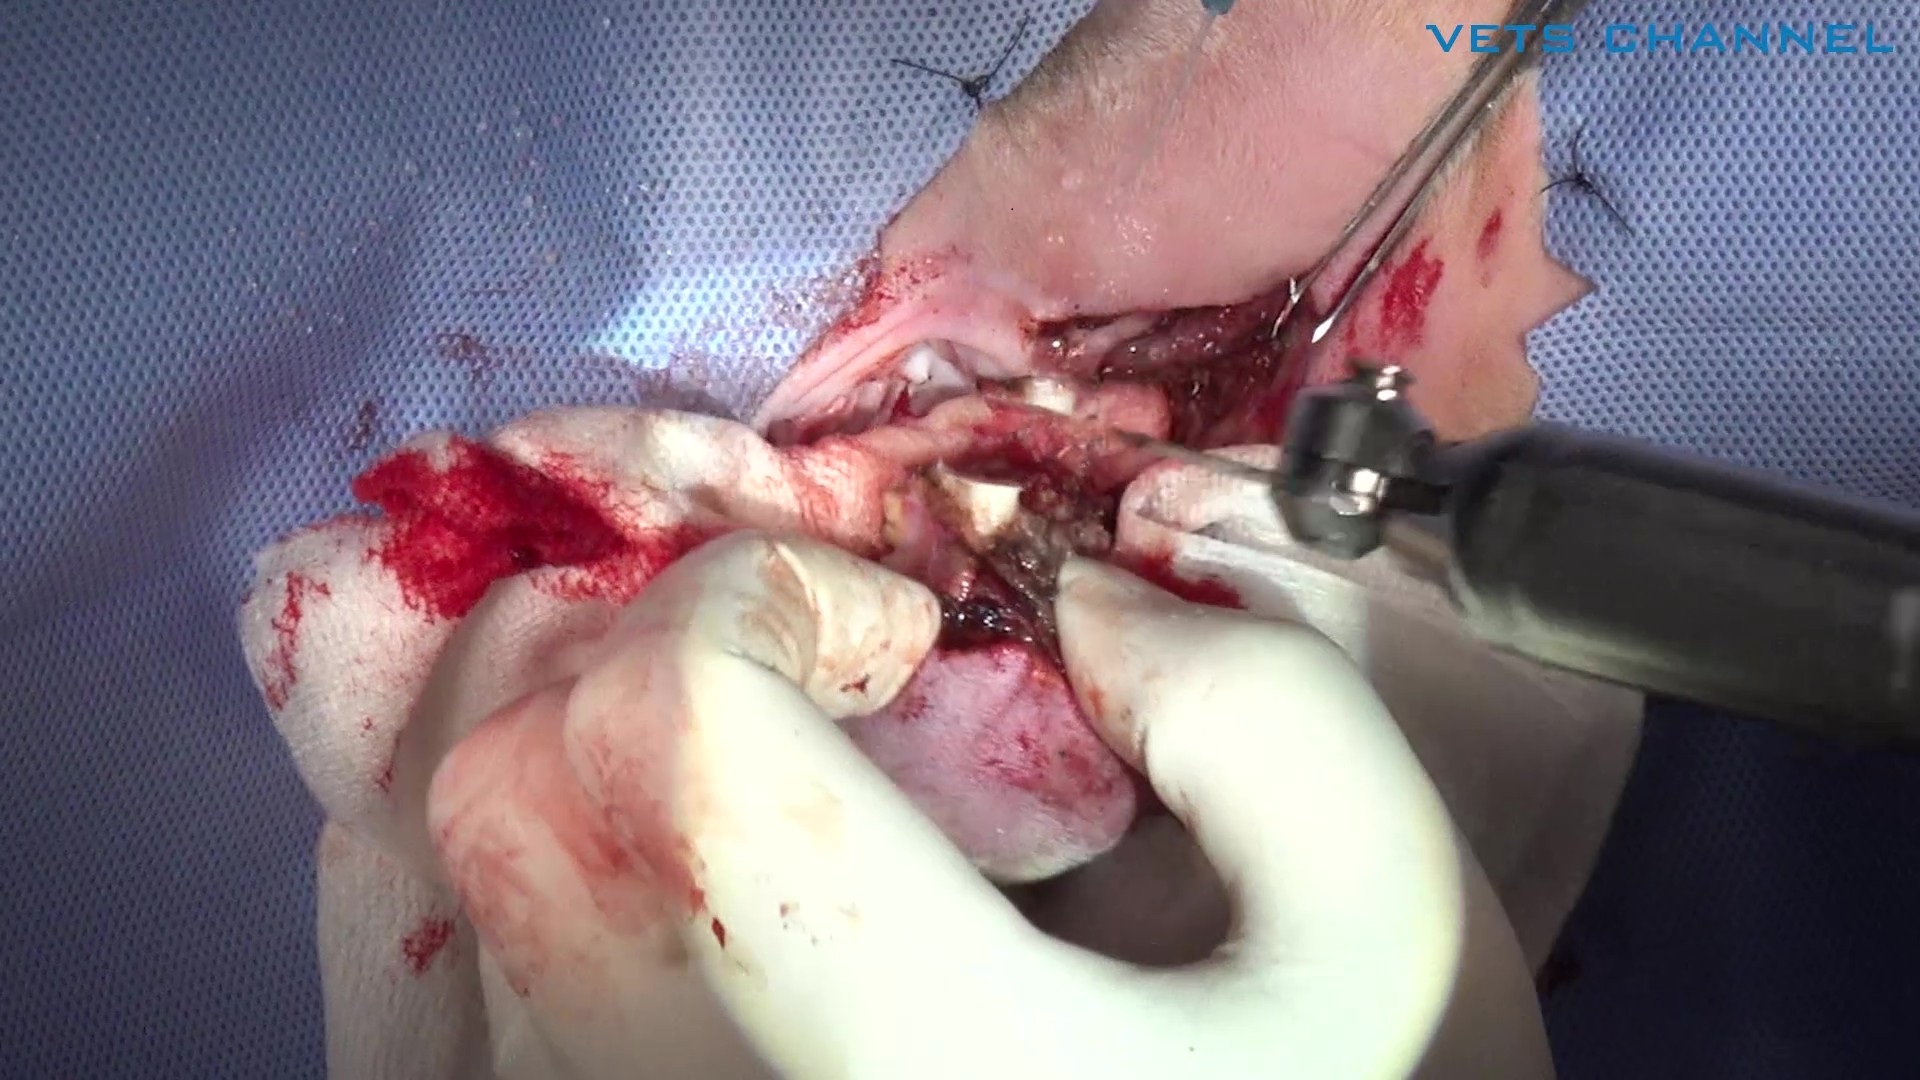

局所再発した扁平上皮癌に対する両側下顎切除術

藤本 晋輔先生 (大津どうぶつ医療センター)

20分

2025/11/14

局所再発した扁平上皮癌に対する両側下顎切除術

藤本 晋輔先生 (大津どうぶつ医療センター)

20分

2025/11/14